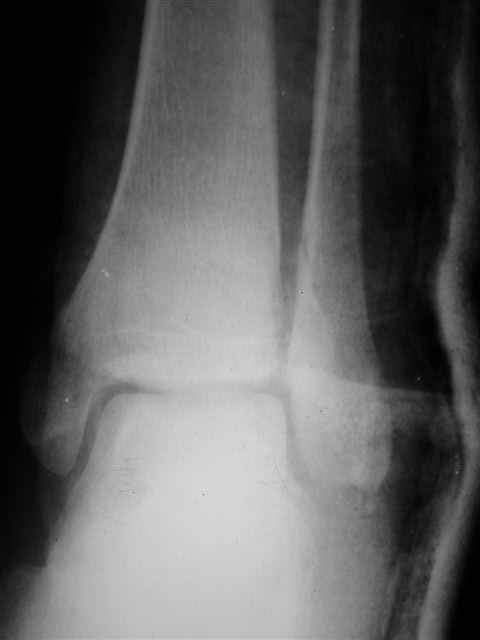

> Если Вас не затруднит, пришлите, пожалуйста, рентгенограммы. Я

> интересуюсь тактикой лечения повреждений голеностопного сустава.

> Хочется посмотреть, как лечат коллеги.

Я предупреждал, что ничего сверхъестественного. Каюсь, что одна из спиц прошла несколько дальше, чем нужно было, но главное - перелом стабилизирован и больной работает суставом в полном объёме, несмотря на представленную раннее травму коленного сустава.